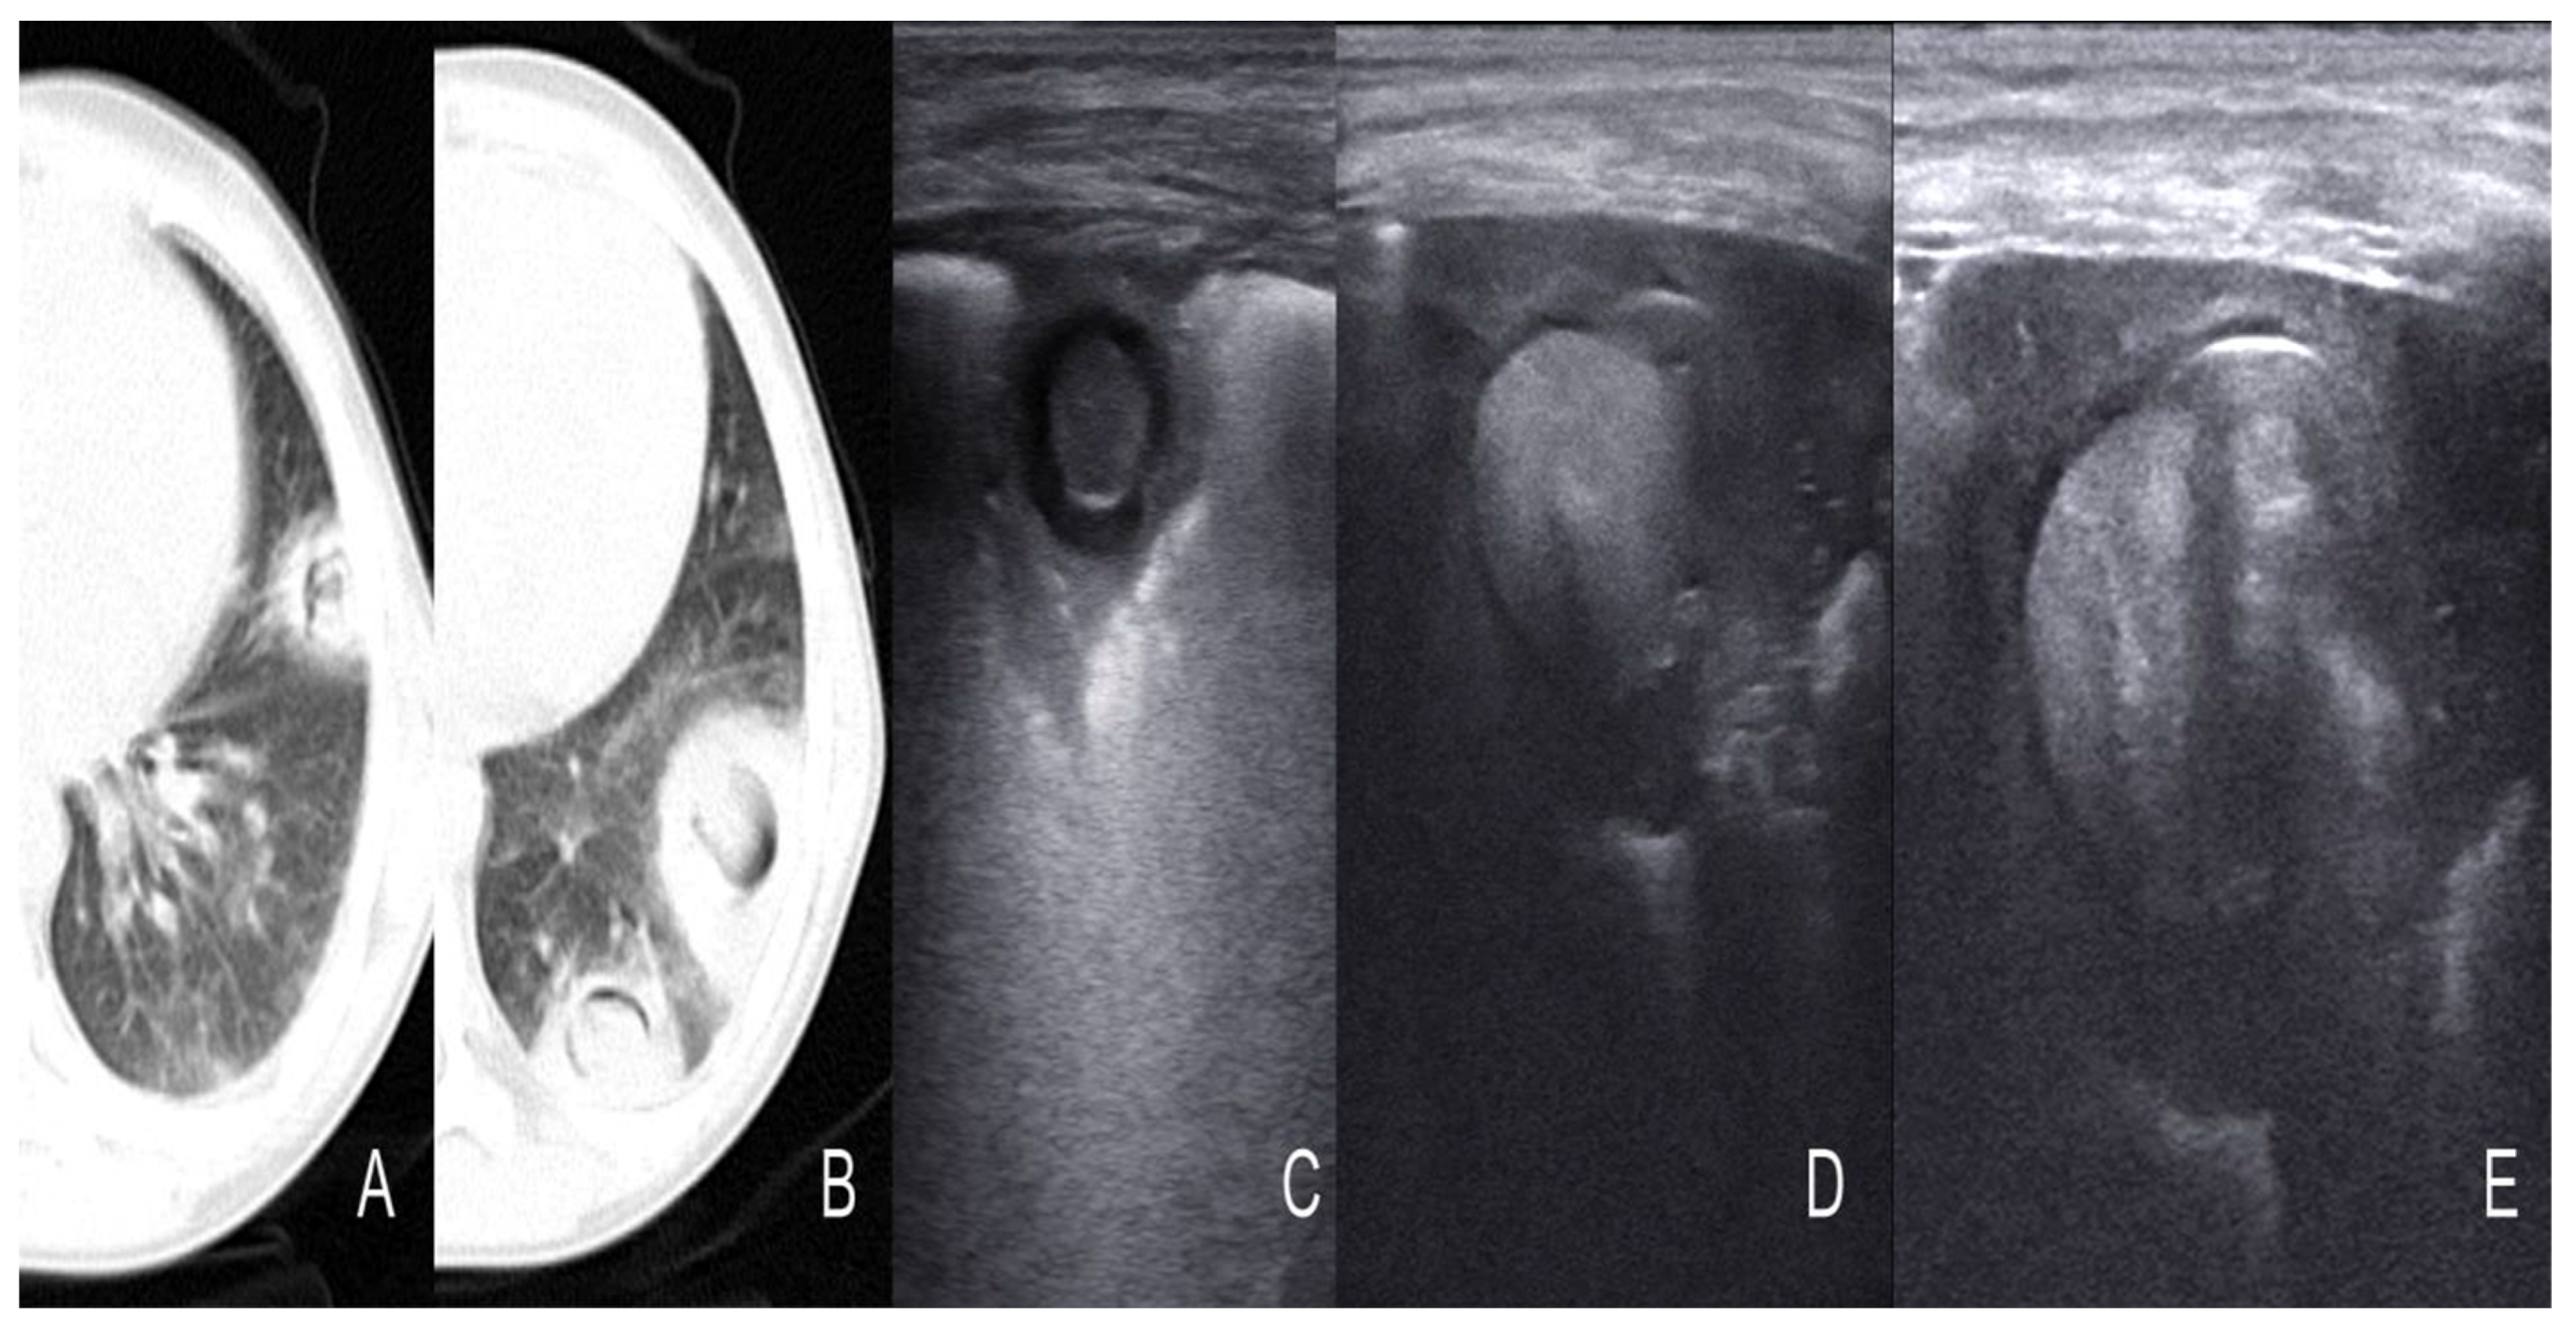

- Garg, M.; Prabhakar, N.; Gulati, A.; Agarwal, R.; Dhooria, S. Spectrum of imaging findings in pulmonary infections. Part 2: Fungal, mycobacterial, and parasitic. Pol. J. Radiol. 2019, 22, 214–223. [Google Scholar] [CrossRef]

| Cavitation | Solid, hypoechoic, heterogeneous lesions with sharp lobulated margins [11,25] |

| Consolidation | Area in which lung tissue is de-aerated with density similar to parenchymal tissues [23] |